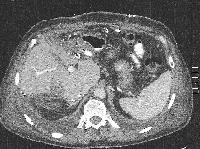

Πρόκειται για ασθενή 75 ετών που διαπιστώθηκε ότι έπασχε από αδενοκαρκίνωμα του σιγμοειδούς με 15 συνολικά ηπατικές μεταστάσεις αμφοτερόπλευρα (εικόνα 1). Η διενέργεια PET-CT δεν ανέδειξε εξωηπατική νόσο. Δεδομένου ότι η πρωτοπαθής εστία τέθηκε υπό προσωρινό έλεγχο με πολυπεκτομή, αποφασίστηκε η αντιμετώπιση πρώτα των μεταστάσεων ("liver first" approach). Με βάση τις εικονικές ηπατεκτομές κατά MEVIS (εικόνα 2) αποφασίστηκε η κάθαρση του ήπατος από το μεταστατικό φορτίο σε δύο στάδια (staged hepatectomy). Ο ασθενής υποβλήθηκε σε 6 κύκλους χημειοθεραπείας (Avastin, FOLFOX). Ακολούθησε δεξιά ηπατεκτομή (εικόνα 3). Κατόπιν υποβλήθηκε σε ακόμα 4 κύκλους χημειοθεραπείας. Η ογκομέτρηση την 4η μετεγχειρητική εβδομάδα ήταν ικανοποιητική (εικόνα 4). Ακολούθησε αριστερή πλάγια ηπατεκτομή (εικόνα 5), η οποία και έφερε την κάθαρση του ηπατικού μεταστατικού φορτίου. Η νέα ογκομέτρηση την 4η μετεγχειρητική εβδομάδα ήταν ξανά ικανοποιητική (εικόνα 6). Συνεχίστηκε η χημειοθεραπεία για ακόμα 4 κύκλους. Ακολούθως, ο ασθενής υποβλήθηκε σε σιγμοειδεκτομή. Τελικά, η χημειοθεραπεία ολοκληρώθηκε με άλλους 6 κύκλους. Ο ασθενής εξακολουθεί να παραμένει ελεύθερος νόσου στους τακτικούς ελέγχους (δις ετησίως) με κολονοσκοπήσεις και CT.